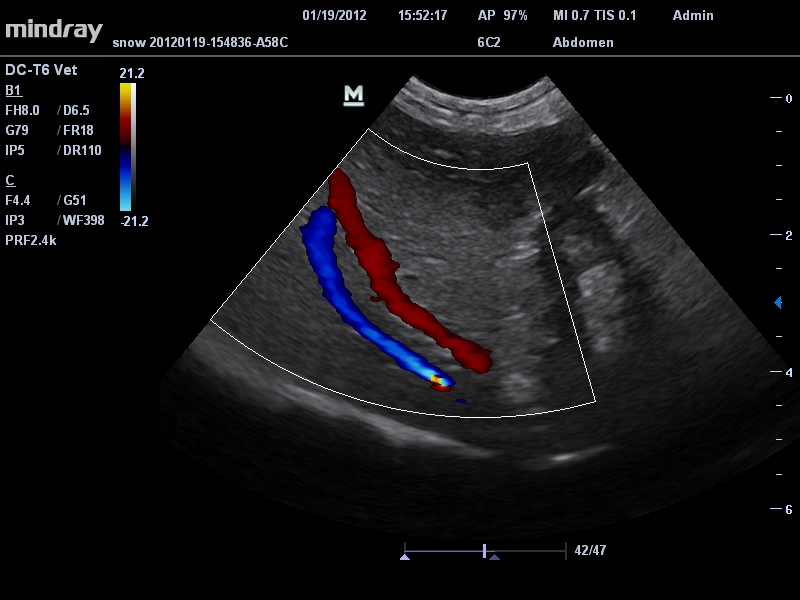

Mindray DC-T6

Ультразвуковая система Mindray DC-T6 – это инновационный аппарат для проведения высокого уровня диагностики с качественной визуализацией и широким спектром применения. Платформа рекомендована для использования в коммерчески многопрофильных медицинских учреждениях и государственных лечебных клиниках.

• Микроконвексный датчик Mindray 6C2